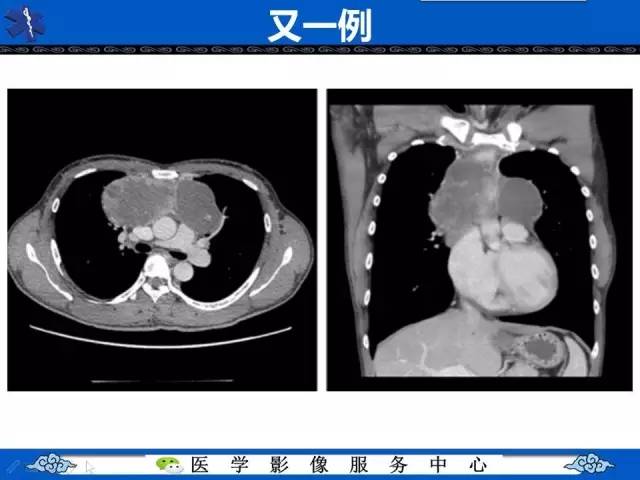

【病例】纵隔内胚窦瘤1例CT影像表现